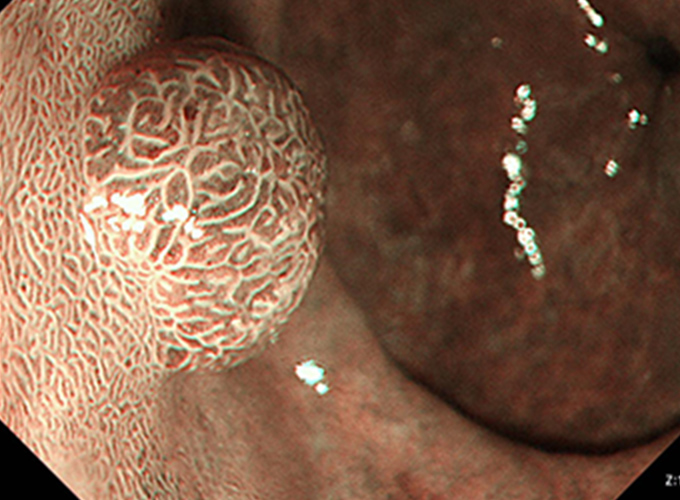

狭帯域光観察:NBI(Narrow Band Imaging)BLI(Blue LASER Imaging)

このシステムでは、狭帯域化された2つの波長の光を用いることにより、発見が困難な病変を見つけたり、がんの範囲の詳細な診断をすることが可能です。 特に、食道がんや咽頭、喉頭のがんはNBIで観察することで、発見の精度が上がります。

内視鏡的粘膜下層剥離術:ESD(Endoscopic submucosal dissection)

専用の処置具を使いより広範囲に病変を切り取ることが可能な治療法です。切り取られた病変は、最終的に顕微鏡でその組織の様子が確認されます(病理検査)。この方法では、大きな病変をひとかたまりで取り、病理検査でより正確な診断を行うことができます。

ESDは大きな病変も一括して切除可能ですが、手技が煩雑で時間がかかり、出血や穿孔などの併発症が生じる場合があります。ほとんどの場合内視鏡的に止血可能ですが、稀には輸血、開腹手術などを要することがあります。

大腸ポリープまたは早期大腸がんの内視鏡治療

良性のポリープや早期がんの中でも粘膜だけにとどまっているもの、粘膜下層へわずかに広がっているものが内視鏡治療の適応となります。 小さなポリープに対しては、鉗子でつかみながら高周波電流を用いて病変の根もとを焼き切ります(ホットバイオプシー)。 茎のあるポリープに対しては、輪の形のスネアを茎の部分でしめ、高周波電流を用いて切断します(ポリペクトミー)。 茎のない病変に対しては、内視鏡的粘膜切除術(EMR)や内視鏡的粘膜下層剥離術(ESD)などを行います。